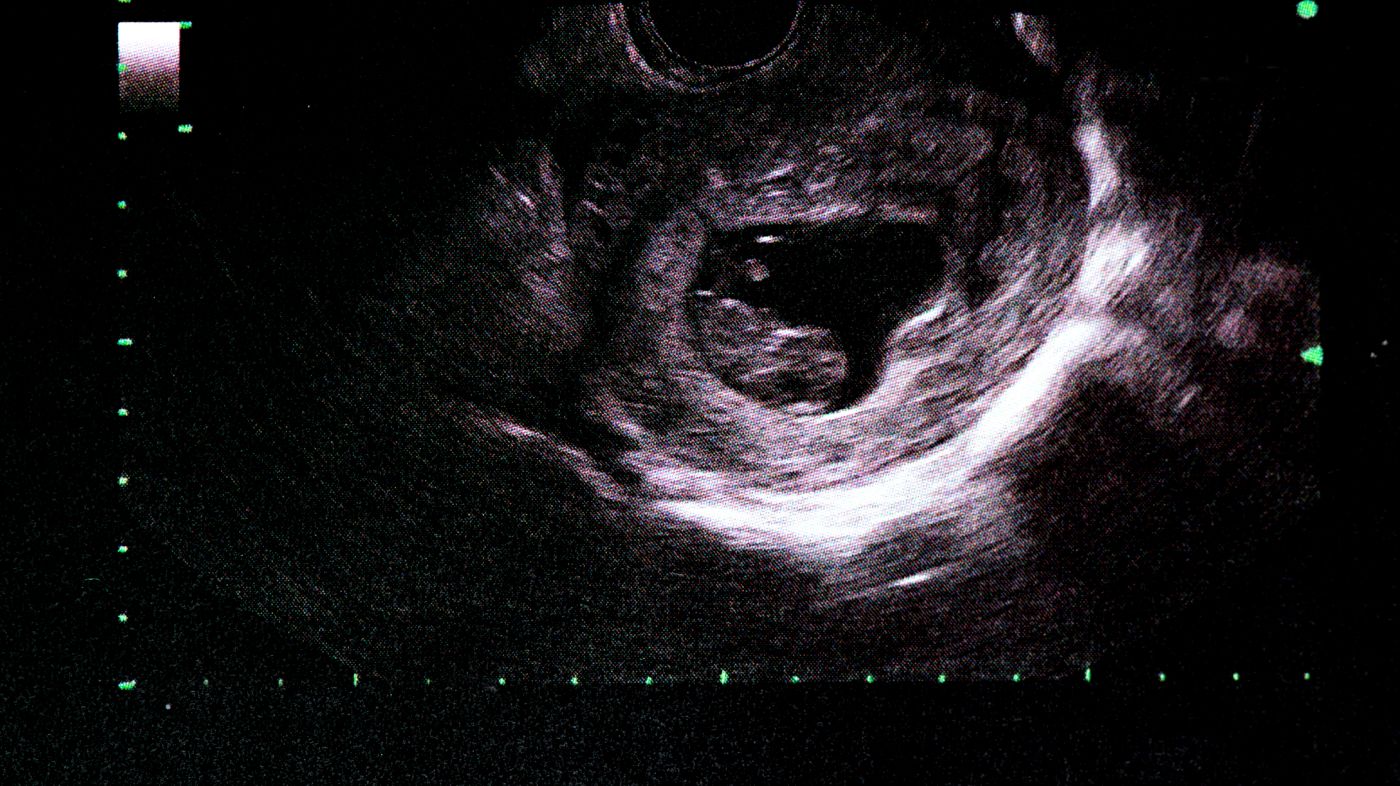

На этой стадии беременности ребенок становится все более осознанным и активным. Узи фотографии показывают, что его плодовой мешок становится уже образованным, а сердцебиение можно услышать с помощью узи аппарата.

Хотя пока еще рано говорить о половой принадлежности ребенка на узи фото, уже можно увидеть формирование его черт лица. Глаза, нос, губы - все более четко проглядывается на узи снимках.